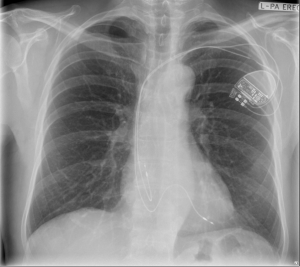

A chest x-ray has been obtained and your opinion is sought regarding how he best be managed.

The electrical findings are consistent with a fracture of the conductor component of the right atrial lead. The chest x-ray demonstrates a macroscopic abnormality of the right atrial lead in the pectoral region, superficial to the second rib. This observation accounts for both the abnormalities observed with electrical interrogation of the lead and provocative arm movement testing.